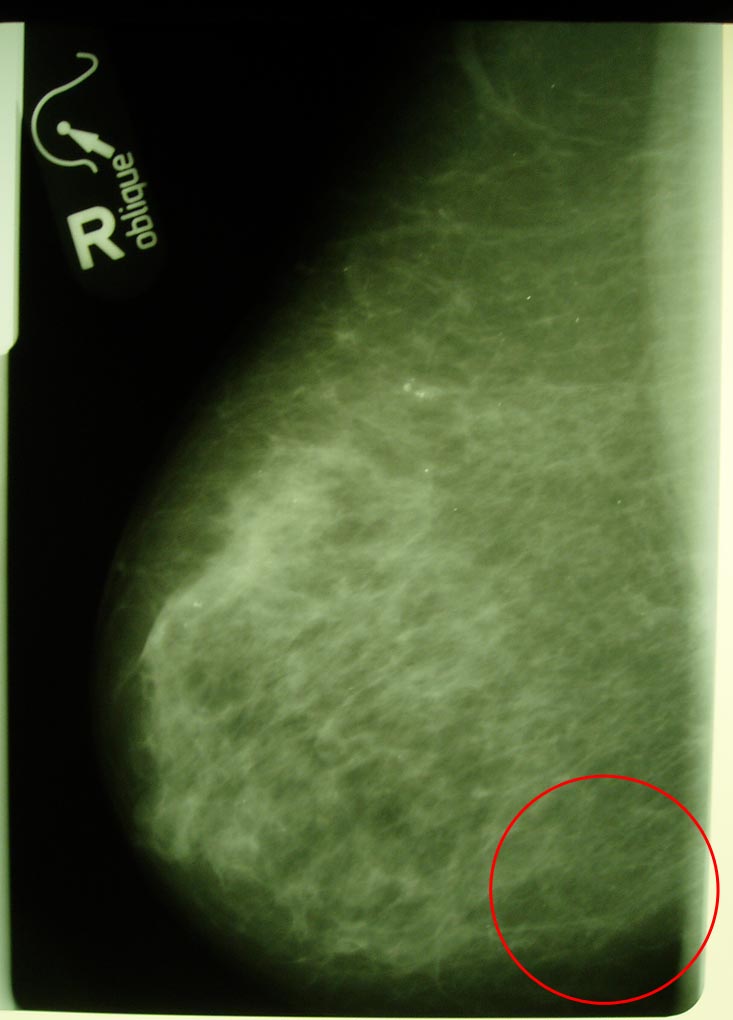

Маммограмма в динамике.

Больная раком правой молочной железы T4аN0M0. Регресс.

11.04.2007 (полтора года лечения и наблюдения)